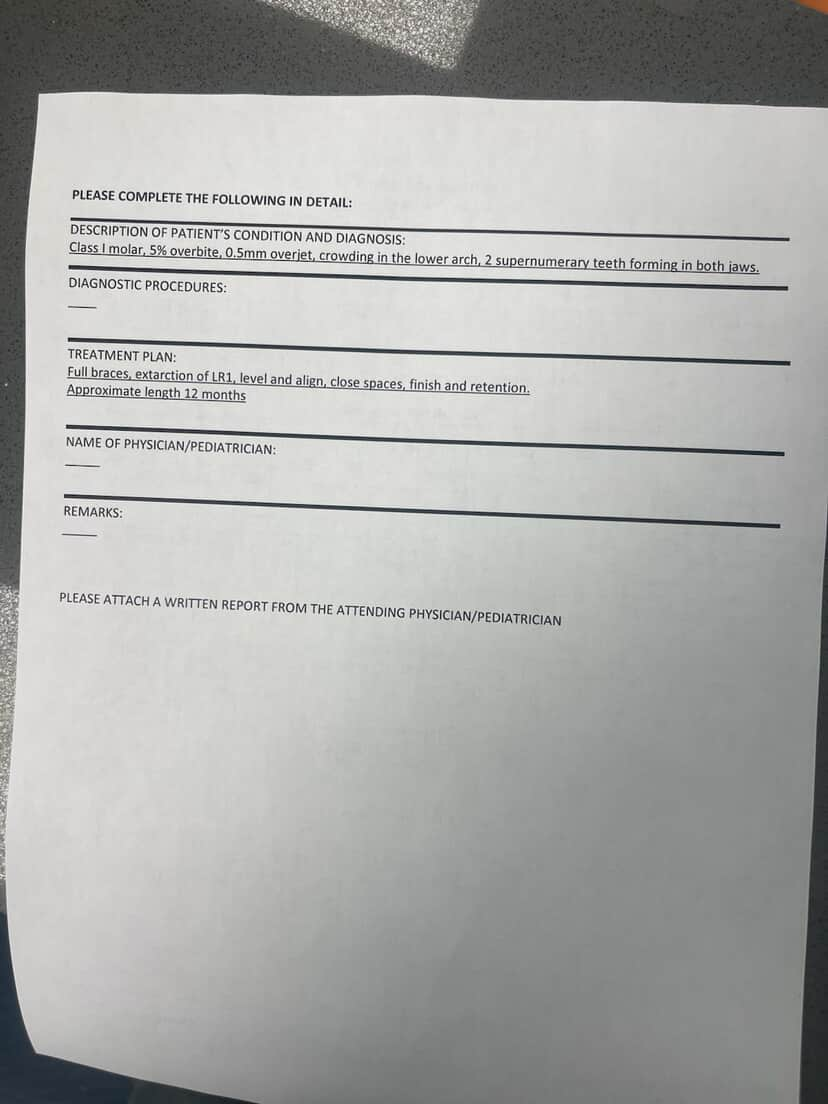

View attachment 4232105 Thoughts on the treatment plan my ortho gave me i just wanna fix my convex profile that i developed thru bad habits is their any diy thing i can do + any advice for my coloring etc

View attachment 4232105 Thoughts on the treatment plan my ortho gave me i just wanna fix my convex profile that i developed thru bad habits is their any diy thing i can do + any advice for my coloring etc

View attachment 4232105 Thoughts on the treatment plan my ortho gave me i just wanna fix my convex profile that i developed thru bad habits is their any diy thing i can do + any advice for my coloring etc

View attachment 4232105 Thoughts on the treatment plan my ortho gave me i just wanna fix my convex profile that i developed thru bad habits is their any diy thing i can do + any advice for my coloring etc

View attachment 4232105 Thoughts on the treatment plan my ortho gave me i just wanna fix my convex profile that i developed thru bad habits is their any diy thing i can do + any advice for my coloring etc

View attachment 4232105 Thoughts on the treatment plan my ortho gave me i just wanna fix my convex profile that i developed thru bad habits is their any diy thing i can do + any advice for my coloring etc